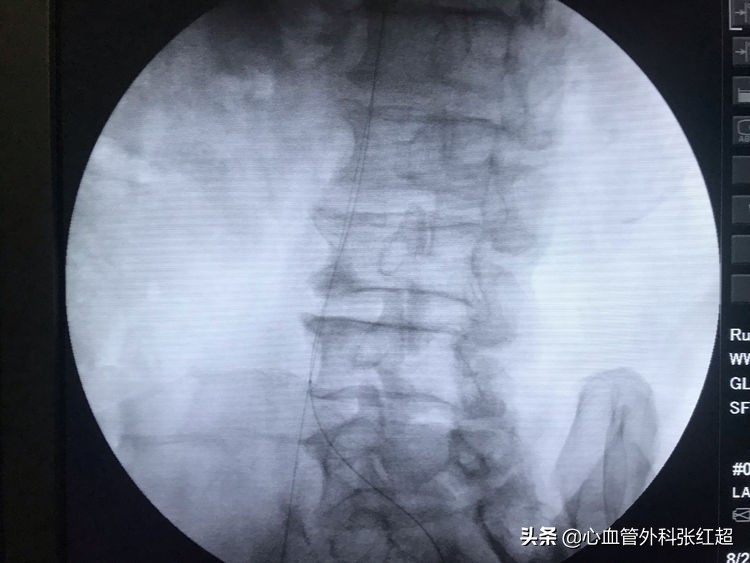

导丝进入假腔方向,加用微导管,换导丝破膜入真腔。

方位验证导丝入真腔后,用微导管造影进一步验证。

送入小球囊扩张,目的:①预防出血;②预防血栓脱落。

扩张时一定关注保持外鞘位置,避免血肿形成。

扩张中患者有痛应终止,防心弯曲部分球囊肩撕性撕裂。

血管造影剂排空快,对侧显影淡,说明血管内血流速度快。

屈曲部稍有残余狭窄。不用硬扩,支架可以在术后贯性序扩。

放两枚支架更容易保证远端释放到位